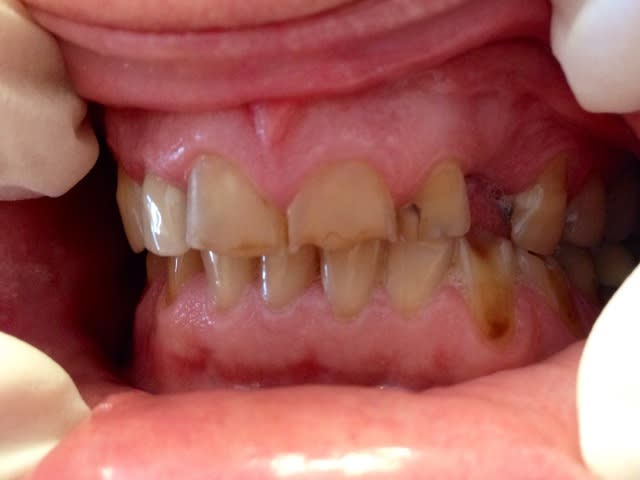

non concordance entre les faces dentaires en diduction et propulsion et les pertes de tissus qui sont plus importantes, érosion probable.

sur tes photo difficile à apprécier.

Sinon il bruxe pas mal c'est sur, il fait des mouvements de grande amplitude en propulsion et en diduction gauche. Ça patine pas mal. Ce qui a du faire claquer l'email au collet de 33 et 34.

Si ce n'était que de l'érosion il aurait le même pb à droite non?